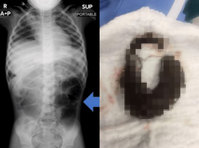

더 건강한 아빠가 되기 위해 연초를 끊고 전자담배를 선택했던 30대 남성이 폐가 허탈된 사연이 전해졌다.지난 16일(현지시각) 외신 피플(People)에 따르면 미국 애리조나주에 거주하는 딜런 보니(34)는 2019년 딸이 태어나기 직전 금연을 결심하며 전자담배를 피우기 시작했다. 그는 “갑자기 담배를 끊기보다는 전자담배를 이용하면 금연 성공 가능성이 더 높을 것이라 생각했다”며 “모든 선택은 딸을 위한 것이었다”고 말했다.이후 보니는 연초보다 냄새가 덜하고 사용이 간편하다는 이유로 전자담배에 더 깊이 의존하게 됐다. 잠을 잘 때도 베개 밑이나 손에 전자담배를 쥔 채 생활할 정도였다. 그러던 어느 날 주방에서 일을 하던 그는 갑작스러운 흉통을 느끼고 바닥에 주저앉았다. 약 1시간 30분가량 통증을 참고 버티다 병원을 찾았지만, 응급실 도착 직후 의식을 잃고 쓰러졌다.검사 결과 오른쪽 폐가 허탈된 상태였고, 곧바로 응급 수술을 받아야 했다. 그는 총 두 차례 수술과 약 2주간의 입원 치료를 받았다. 보니는 “전자담배 과사용이 폐 손상의 주요 원인이라는 설명을 들었다”고 했다.폐허탈은 폐 속 공기가 새어 나와 폐가 원래 크기만큼 팽창하지 못하고 쭈그러드는 상태를 말한다. 대표적으로 기흉이나 무기폐가 발생했을 때 나타날 수 있다. 특히 기흉은 갑작스러운 가슴 통증과 호흡곤란, 청색증 등을 유발할 수 있는 응급 질환이다.흡연은 자발성 기흉의 대표적인 위험 요인 중 하나로, 실제로 외상없이 발생하는 자발성 기흉 환자 가운데 흡연자의 비율이 높은 것으로 알려져 있다. 전자담배는 연초와는 다른 방식으로 폐에 급성 손상을 일으킬 수 있다. 전자담배는 냄새가 덜하고 사용 제약이 상대적으로 적어 더 자주, 오래 흡입하게 되는 경우가 많다. 이 과정에서 폐 조직은 고농도의 화학물질에 쉴 새 없이 노출된다. 특히 전자담배의 미세 입자는 기도에서 걸러지지 않고 폐의 가장 깊숙한 곳인 폐포까지 직접 침투해 광범위한 염증을 일으킨다.특히 전자담배 관련 폐 손상(EVALI)은 단기간에도 급성 폐부전이나 기흉 같은 심각한 합병증으로 이어질 수 있어 주의가 필요하다. 실제로 미국 질병통제예방센터(CDC) 연구에 따르면 2020년 초까지 미국에서 전자담배 관련 폐 손상으로 약 2800명이 입원했고, 68명의 사망 사례가 보고됐다.

세 살 딸의 배가 단순히 부은 줄 알았던 엄마가 병원 검사 끝에 희귀 소아암 4기 진단을 받게 된 사연이 공개됐다.최근 미국 매체 뉴스위크에 따르면, 호주 퀸즐랜드에 사는 재즈민 스프링(20)은 15세에 임신해 16세에 엄마가 됐다. 그는 “어린 나이에 아이를 키우는 것이 인생 최대의 어려움일 줄 알았지만, 그것은 시작에 불과했다”고 말했다. 현재 세 살이 된 딸 올리비아는 밝고 활발한 아이였고, 모녀는 늘 함께 시간을 보냈다.그러던 중 올해 초, 재즈민은 딸의 배가 평소보다 부어 보인다는 사실을 알아차렸다. 손으로 만져보니 배 한쪽이 다른 쪽보다 유독 단단하게 느껴졌다. 그는 처음에는 변비나 단순 복부팽만이라고 생각했다. 그러나 이상하다는 느낌을 지울 수 없어 병원을 찾았다.의료진은 올리비아 복부에서 덩어리를 확인했고, 아이는 호주 퀸즐랜드 어린이병원에서 초음파·CT·엑스레이 등 여러 검사를 받았다. 검사 결과는 충격적이었다. 왼쪽 신장에 약 12cm크기의 종양이 발견됐고, 부신과 간에서도 종양이 확인됐다. 이후 검사에서는 폐 전이 병변 3개까지 발견됐다. 일부 종양은 파열된 상태였고, 복부 주요 혈관을 감싸고 있어 수술도 쉽지 않은 상황이었다.결국 올리비아는 희귀 소아 신장암인 ‘윌름스종양’ 4기 진단을 받았다. 윌름스종양은 주로 5세 이하 영유아에게 발생하는 신장암으로, 조기에 발견하면 치료 성적이 비교적 좋은 편이지만 전이가 진행된 경우 치료가 복잡해질 수 있다.재즈민은 “진단받은 날은 내 스무 번째 생일이었다”며 “믿기지 않았고, 계속 울다가 몸 상태까지 나빠졌다”고 말했다. 그는 “내 아이에게 이런 일이 생길 거라고는 누구도 생각하지 못한다”고 했다.암이 이미 상당히 진행된 상태였던 만큼 치료는 곧바로 시작됐다. 올리비아는 6주간 항암치료를 받았고, 종양 제거를 위한 대수술도 진행했다. 약 9시간에 걸친 수술 끝에 의료진은 신장과 부신을 제거했고, 암이 퍼진 장 주변 조직 일부도 함께 절제했다. 종양이 주요 동맥과 정맥을 감싸고 있어 수술 과정은 더욱 까다로웠다.현재 올리비아는 복부와 폐를 대상으로 방사선 치료를 앞두고 있다. 약 3주간 매일 전신마취를 받은 뒤 치료를 이어가야 하며, 이후에도 최소 8개월 이상 추가 치료가 예정돼 있다.재즈민은 “지난 몇 달 동안 딸은 평생 겪을 고통을 압축해 겪은 것 같다”고 말했다. 항암치료로 구토와 극심한 피로를 겪고 머리카락도 빠졌지만, 올리비아는 여전히 웃음을 잃지 않는다고 했다. 치료 중에도 손가락으로 ‘브이(V)’ 포즈를 하는 딸의 모습을 보며 버틴다는 것이다.그는 “예전엔 놀이터에서 춤추고 옷놀이를 하며 시간을 보냈지만, 지금 딸은 병동 구조를 외울 정도로 병원에 오래 머문다”며 “아이의 고통을 대신해 줄 수 없다는 게 가장 괴롭다”고 말했다. 이어 “딸은 내 전부이자 가장 친한 친구”라며 “언제나 곁을 지킬 것”이라고 했다.한편 재즈민은 윌름스종양에 대한 인식을 높이기 위해 SNS를 통해 딸의 투병 과정을 기록하고 있다. 가족은 치료와 이주 비용 부담으로 모금 활동도 진행 중이다.